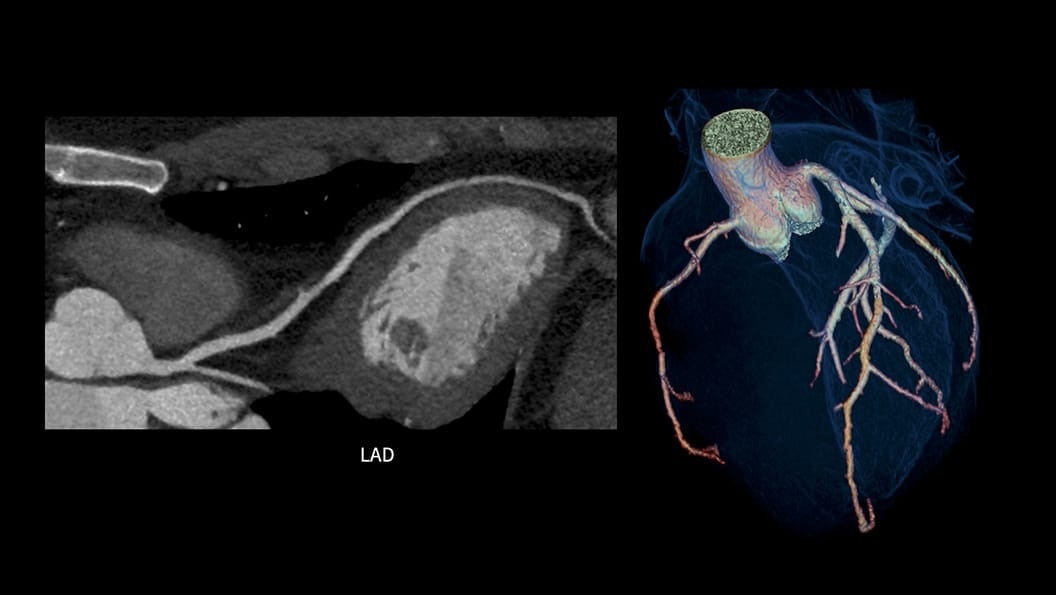

ECG-less Cardiac CT

By removing the need for ECG traces, this innovative technology streamlines patient preparation, saving valuable time and reducing the complexity of Cardiac CT procedures.

4-ecg-less-cardiac-ct-coronary-visualization